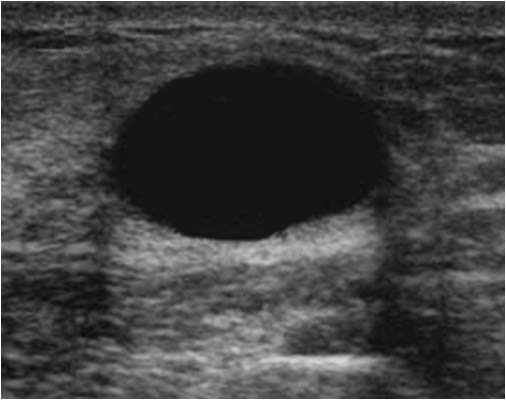

SIGNO DEL HALO EN LA MAMA

La buena delimitación de las lesiones mamarias en la mamografía, rodeadas de un fino halo hipodenso, fue erróneamente considerada durante mucho tiempo como signo de benignidad.

En este caso, la ecografía confirma que se trata de una lesión quística. Pero también algunas lesiones sólidas, tanto benignas como malignas, pueden presentar este signo.

El interés de mostrarlo es para insistir en su inespecificidad.

Puedes consultar en artículo de Cupples TE, Eklund GW y Cardeñosa G. Mammographic halo sign revisited. Radiology 1996; 199:105-108.